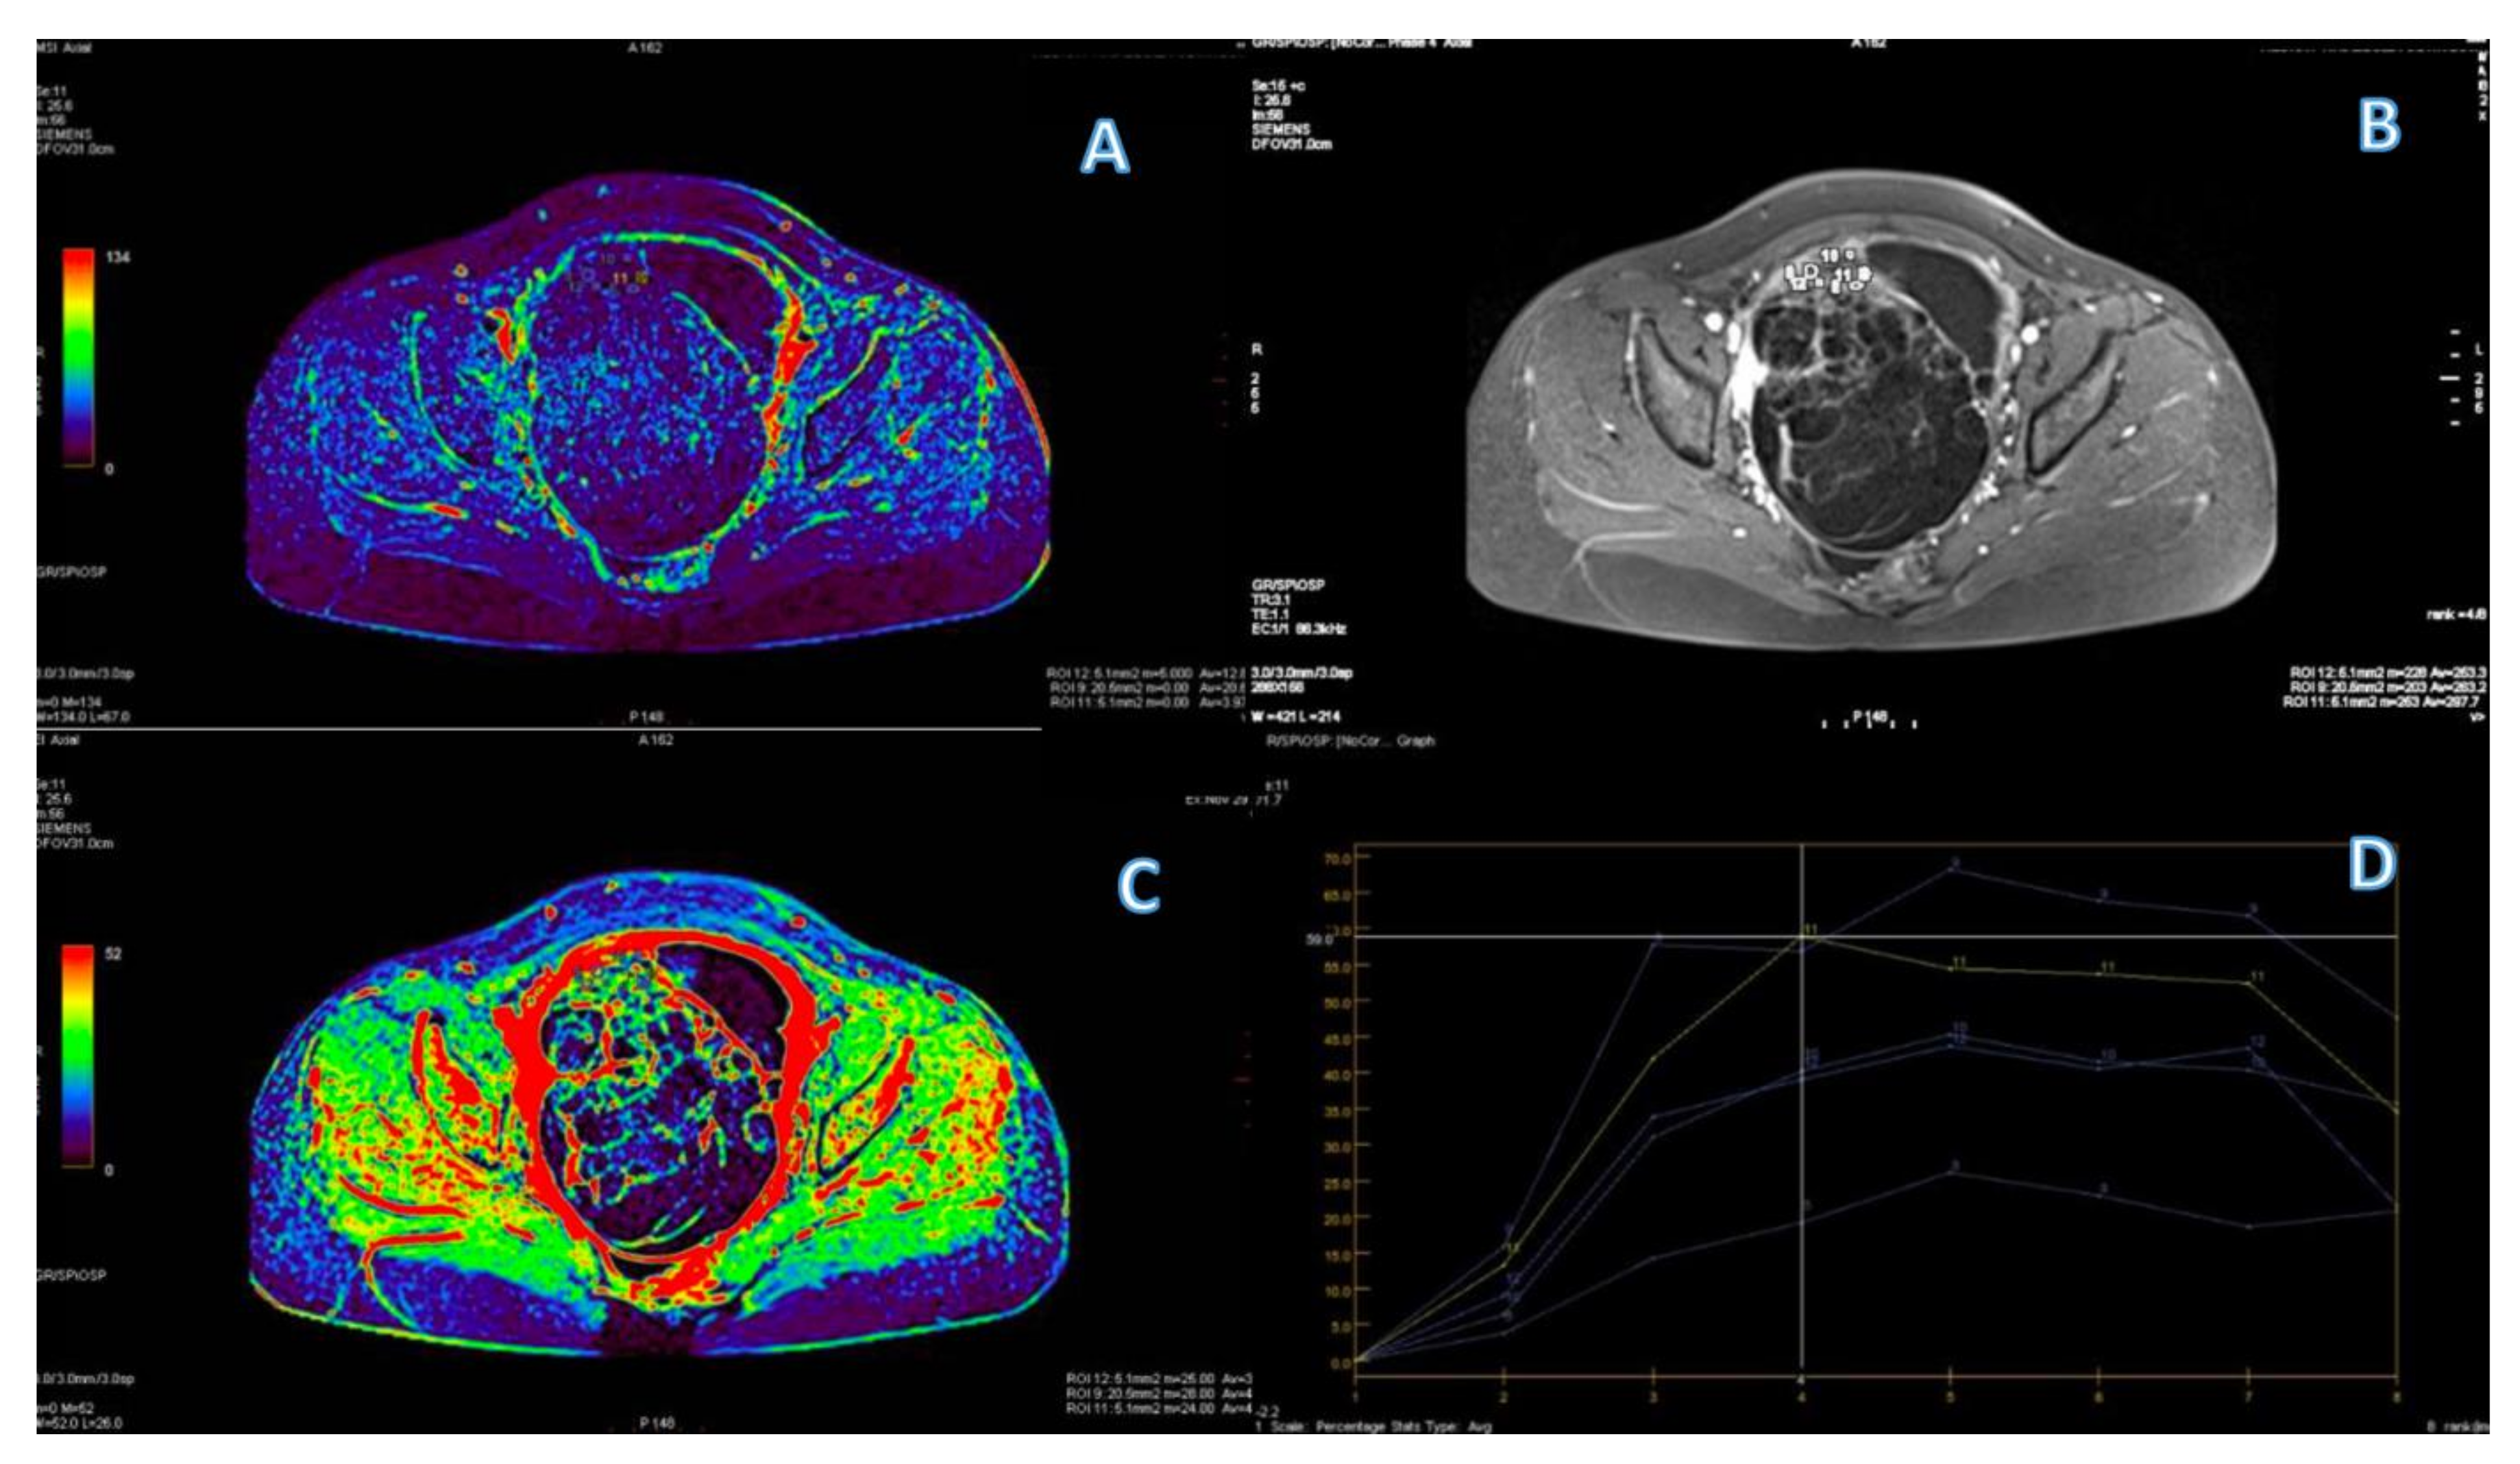

3.1. Primary Tumor DWI

3.3. Primary Tumor DCE

3.4. ROC Curve for LGSC vs. MOC

3.5. ROC Curve for HGSC vs. MOC